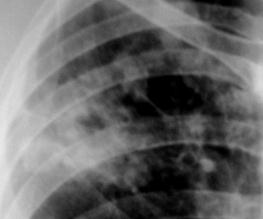

Рис.1. Очаговые тени